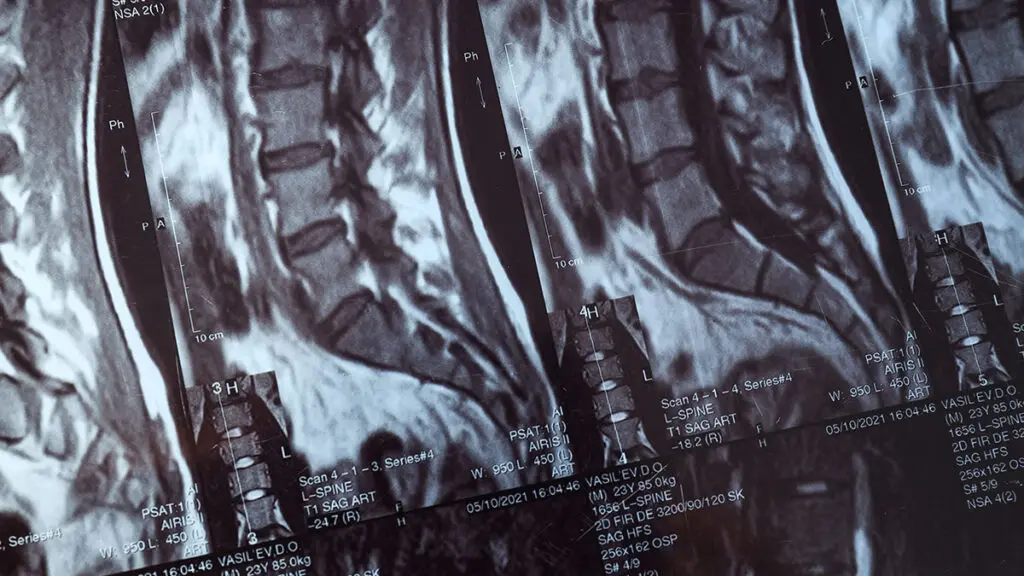

Global Spine Solutions è il clinica neurochirurgica di eccellenza della capitale, specializzato in neurochirurgia spinale mininvasiva. Il nostro team multidisciplinare opera con tecnologie all'avanguardia per diagnosi accurate e trattamenti efficaci di tutte le principali patologie vertebrali, dal dolore lombare cronico alle condizioni neurologiche più complesse.

Come clinica neurochirurgica, Global Spine Solutions accompagna il paziente lungo l'intero percorso di cura: dalla prima valutazione clinica, attraverso la pianificazione del trattamento conservativo o chirurgico, fino alla riabilitazione post-operatoria, garantendo continuità assistenziale e risultati misurabili.